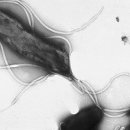

십이지장궤양 등 소화성 궤양의 원인에 대한 종전의 관념을 깨는 발표가 있었습니다. 나쁜 식습관과 스트레스가 아니라 헬리코박터균이 원인이라는 설은 등장해 비상한 관심을 모은 것이죠. 헬리코박터는 같은 해 한 워크숍에서 발암 물질로 분류되었다...

긴 글은 못쓰겠고, 혹시 모르시는 분들을 위해 조금만쓰겠습니다, 우리 나라 남성, 열명중 일곱명은 헬리코박터균에 감염이 되여있다고 합니다, 전염성이 굉장히 강하고 약으로는 항암 치료제 항생제를 쓴다고 합니다,헬리코박터균에의해서 위염 위계양...

줄어들어 전염성 질환의 경우에는 전파 가능성이 급격히 떨어지므로 거의 박멸이 되는 것이죠. 헬리코박터 감염의 경우 점차 위생 수준이 높아지면서 젊은 층에서는 점점 감염률이 감소하고 있습니다. 여기에 효과적인 백신을 더해 박테리아의 침투를 막을...